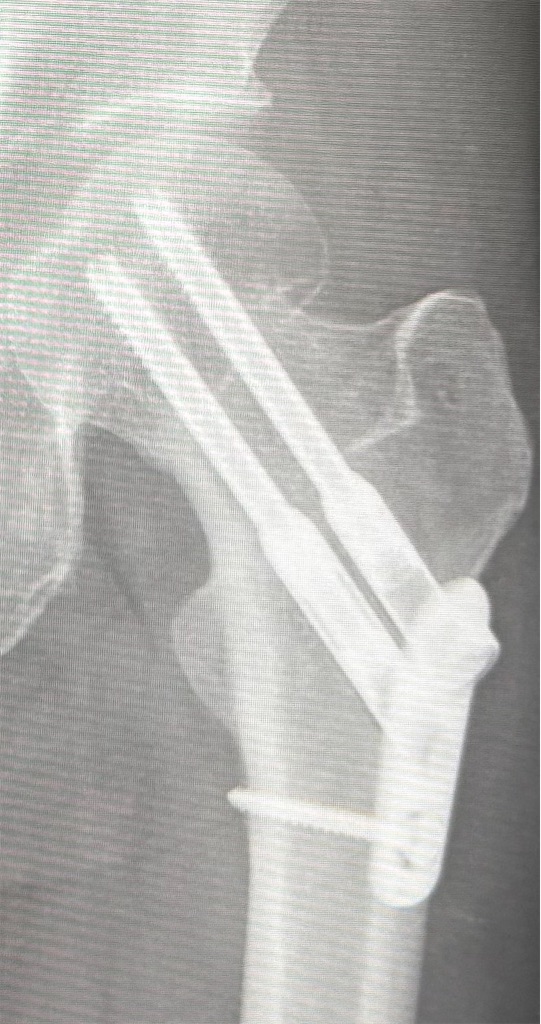

ちなみに私のした骨接合術はこんな感じでした。↑↑

骨折を受け入れるのに時間がかかり自分のレントゲン写真を写メさせてもらう余裕もなかったので…次回の診察で撮らせていただこうかな…

撮らせてもらいました。